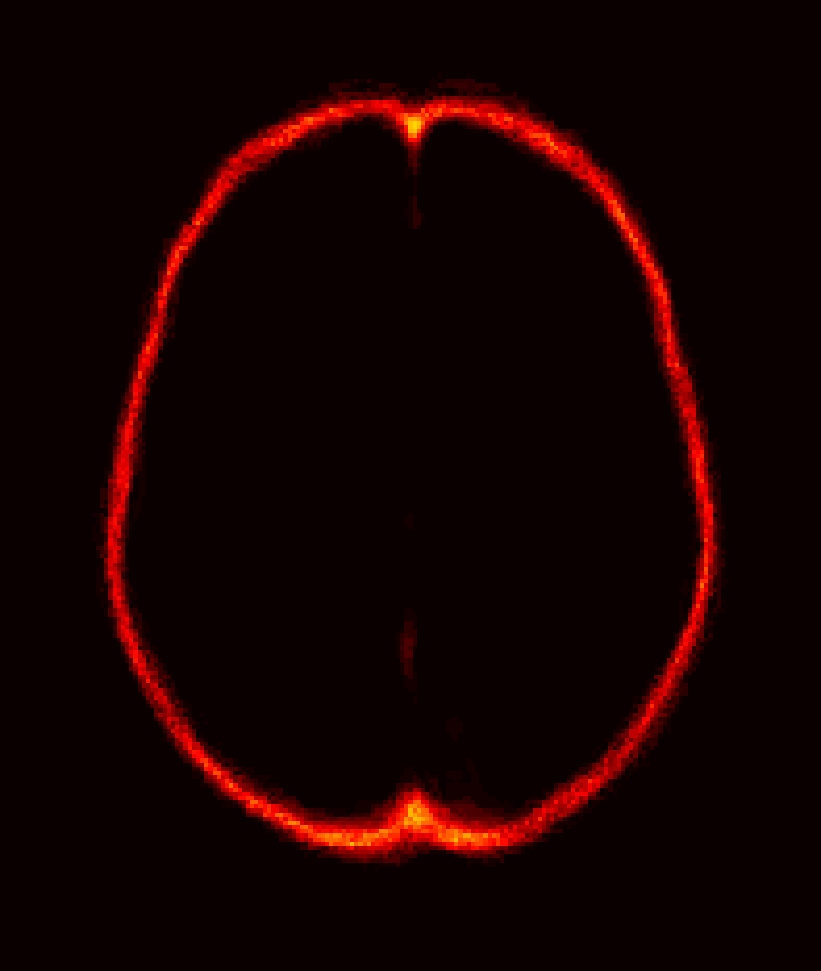

Fig. 1 shows example images from each dataset to illustrate image variability. IBSR and LPBA40 contain images from normal subjects and include large portions of the neck; BRATS has very low out-of-plane resolution; and the TBI dataset contains large pathologies and abnormal skulls.

Refer to caption

Figure 1: Illustration of image appearance variability on a selection of images from each (evaluation) database. From top to bottom: IBSR, LPBA40, BRATS and TBI.